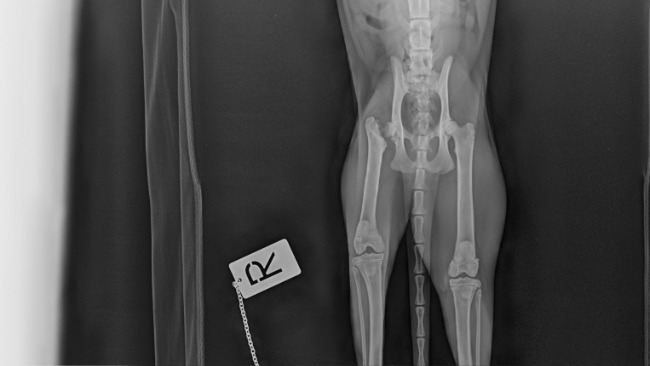

W międzyczasie zauważyłam jednak, że Pola delikatnie kuleje na tylną prawą łapę. A podczas głaskania wyczułam, że kości w okolicach biodra są niesymetryczne, z jednej strony bardziej wystają. Dlatego też, przy okazji zabiegu kastracji, by nie poddawać kotki niepotrzebnie dwukrotnie narkozie, zostało przeprowadzone RTG biodra. Wykazało ono, że Pola ma złamaną szyjkę kości udowej. Być może w przeszłości uległa jakiemuś wypadkowi, bądź ktoś ją kopnął. Tego nie wiem...

Teraz Polę czeka dekapitacja szyjki kości udowej. Operacja została wstępnie wyceniona na minimum 1 000 zł, do tego dochodzą jeszcze leki przyjmowane po operacji i wizyty kontrolne.